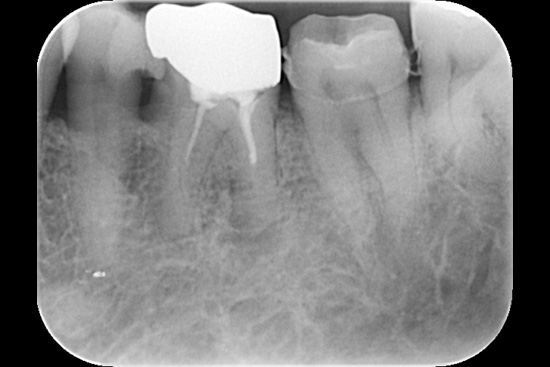

| 主訴 | 左下奥歯の痛み |

| 治療期間 | 2ヶ月 |

| 治療内容 | 根管治療 |